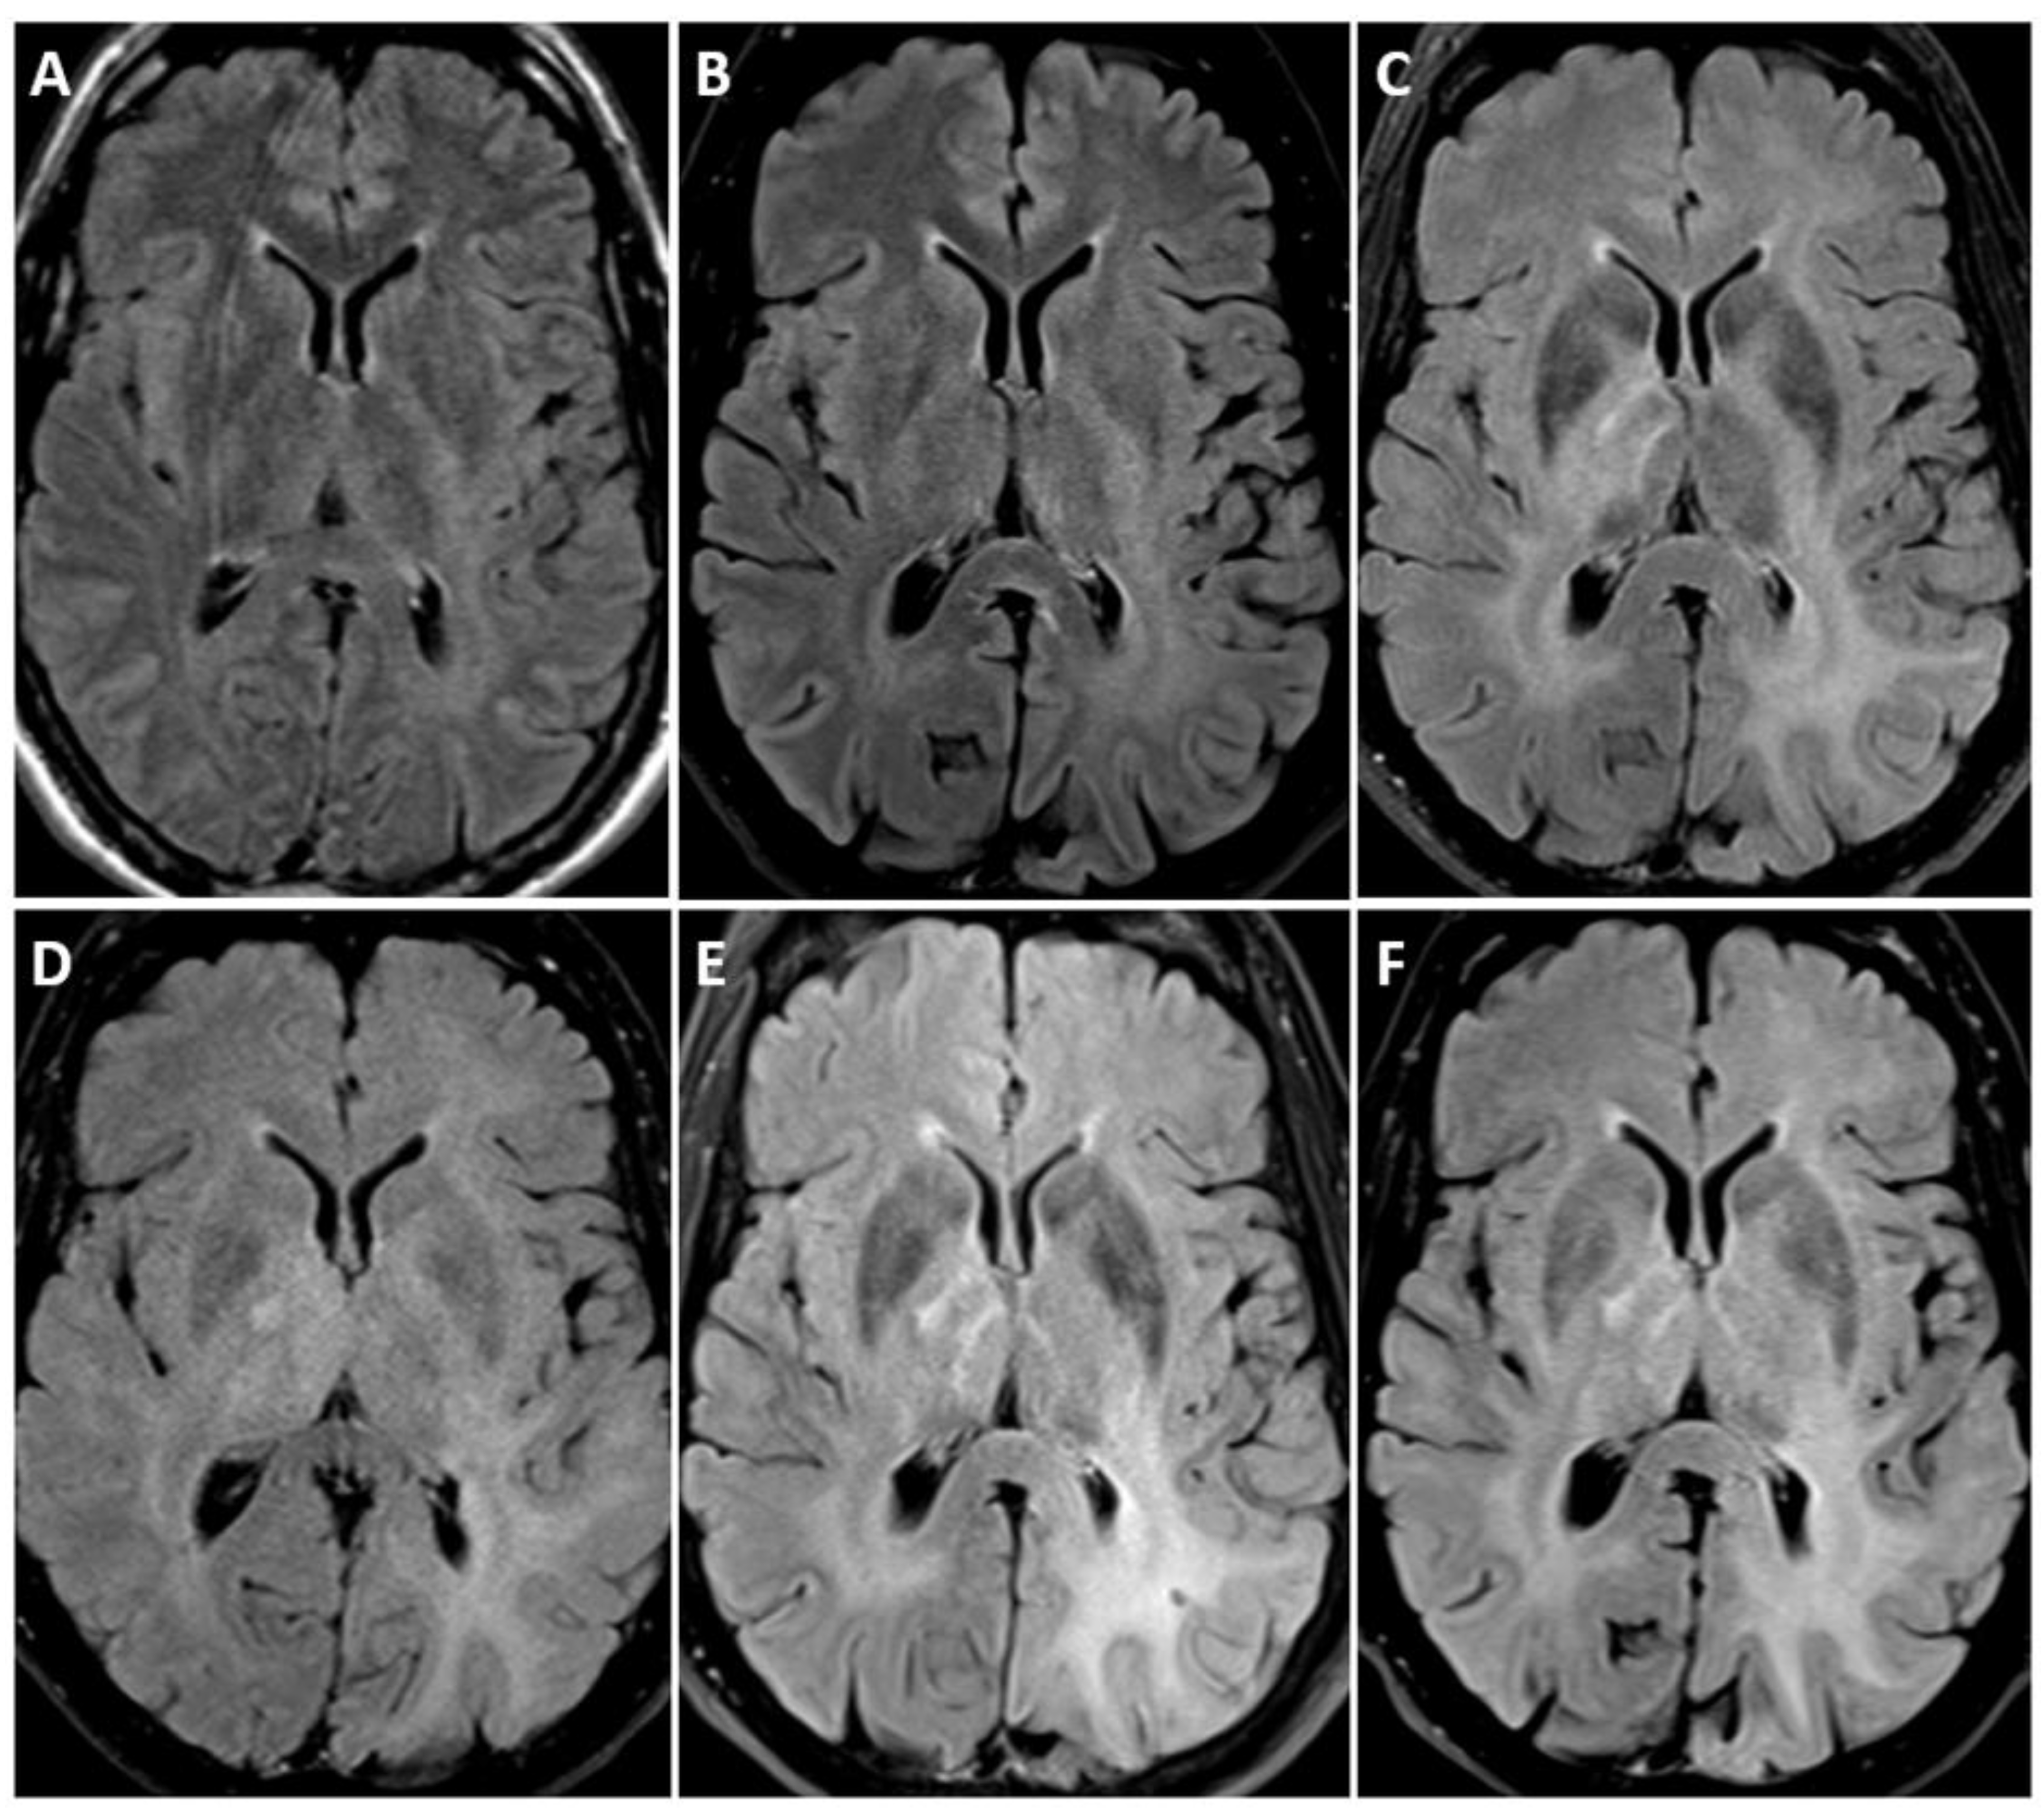

- Aboian, M.; Solomon, D.; Felton, E.; Mabray, M.; Villanueva-Meyer, J.; Mueller, S.; Cha, S. Imaging Characteristics of Pediatric Diffuse Midline Gliomas with Histone H3 K27M Mutation. Am. J. Neuroradiol. 2017, 38, 795–800. [Google Scholar] [CrossRef] [PubMed]

| Diffuse midline glioma, H3 K27-altered | H3 K27, TP53, ACVR, PDGFRA, EGFR, EZHIP | Name changed from H3K27-mutant, | Variable, ill-defined, infiltrative masses, in brainstem, thalamus, or spinal cord, frequently no enhancement, H3.1 subgroup-necrosis and edema likely. |

| Subgroups recognized | |||